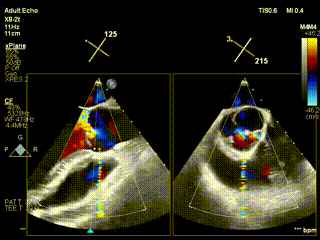

后附病例2、3术前术后视频:

视频3:病例2术前心超提示大量主动脉瓣反流

视频4:病例2 术后无反流

视频5:病例3术前大量主动脉瓣反流

视频6:病例3术后未见反流